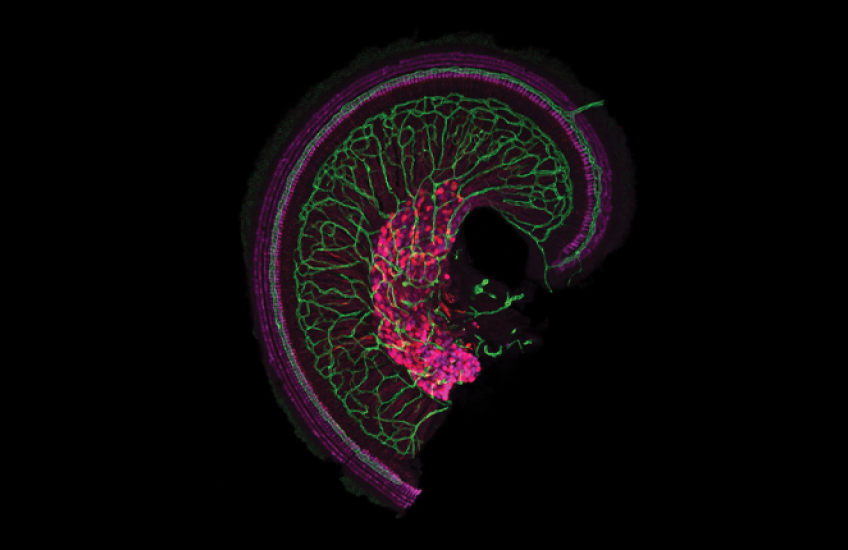

Hair cells, shown in magenta, in the snail-shaped cochlea of the inner ear. Image: Katelyn Comeau

The OTOF gene encodes the otoferlin protein, produced by cells in a snail-shaped part of the inner ear called the cochlea. In the cochlea, sound waves are translated into electric pulses carried by nerve cells to the brain, where they are interpreted as sound. Otoferlin plays a role in transmitting pulses from cochlear cells to the nerves and without it, sound is translated into electric signals but never reach the brain.